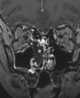

Turbinate enlargement